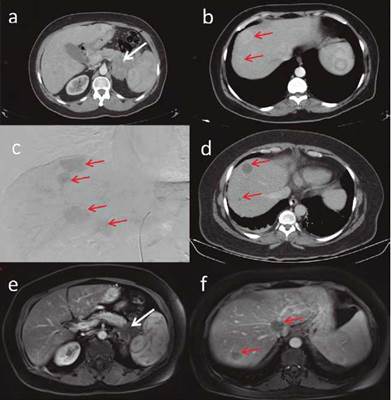

Figura 1 Escanografías abdomen con medio de contraste: (a) Masa lobulada sólida con calcificaciones en cola del páncreas, envuelve vasos esplénicos, diámetros mayores en plano axial de 95 x 45 mm. (b) Metástasis hepáticas la mayoría hipervasculares. (c) Arteriografía embolización: cateterización segmentaria hepática derecha muestra. (d) Imagen postembolización: ausencia de realce como respuesta al tratamiento compromiso metastásico multifocal predominio lóbulo hepático derecho. Resonancia magnética abdomen superior con gadolinio. (e) Masa en cola de páncreas con escaso realce, su tamaño se mantiene. (f) Lesiones focales hepáticas sin realce con gadolinio como respuesta al tratamiento.

Se inició diazóxido con titulación progresiva en la dosis. Por la persistencia de las hipoglucemias se le adicionó prednisolona (10 mg día) con reducción de la frecuencia de los episodios de hipoglucemia a menos de 3 a la semana. El control tomográfico en el ciclo 5 de quimioterapia demostró enfermedad estable (criterios RECIST 1.1); sin embargo, por la persistencia de hipoglucemias se realizó embolización transarterial de las metástasis hepáticas con microesferas de 100 - 300 micras. En la tomografía de control, se observaron cambios en las características de las metástasis hepáticas de una apariencia sólida a quística y ausencia del realce en la fase arterial como respuesta al tratamiento instaurado (fig. 1c y 1d). En el ciclo 7 de quimioterapia la paciente se mantuvo sin nuevos episodios de hipoglucemia, por lo cual se retiró el diazóxido y la prednisolona de manera gradual.

En el ciclo 15 de quimioterapia la paciente presenta poliuria y polidipsia, con glucemia en 329 mg/dL y HbA1c 12%, confirmando el diagnóstico de diabetes mellitus de novo y requiriendo manejo con insulina en esquema basal bolo; las imágenes de control (fig. 1e y 1f) fueron compatibles con enfermedad estable. Se consideró retirar la quimioterapia al obtener una adecuada respuesta clínica.